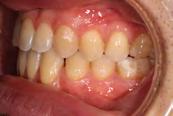

Approximately six months after insertion of the RPE, digital scans were taken for SureSmile custom wires and the patient was scheduled for the SFOT procedure with the oral surgeon. The RPE was removed, SureSmile wires inserted and segmental corticotomies performed, immediately followed by further vertical elastics on the right side (Figure

4). Archwires were upgraded incrementally into 19 x 25 SS. Once the bite was completely closed, the patient was referred to the myofunctional therapist to begin treatment. Eight sessions of myofunctional exercises were performed, focusing on muscle building, toning, synchronicity and awareness. Improvement in correct chewing, swallowing and resting postures of the lip and tongue were addressed. All appliances were removed 21 months after initial insertion (Figure 5), and the patient was referred to a re-

Figure 4. Post-corticotomy, with SureSmile custom wires.